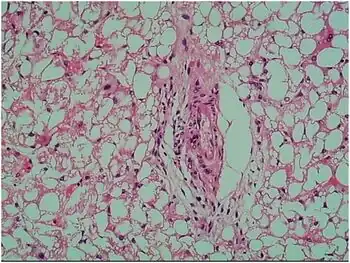

| Staining of liver tissue shows extensive vacuolar degeneration | |